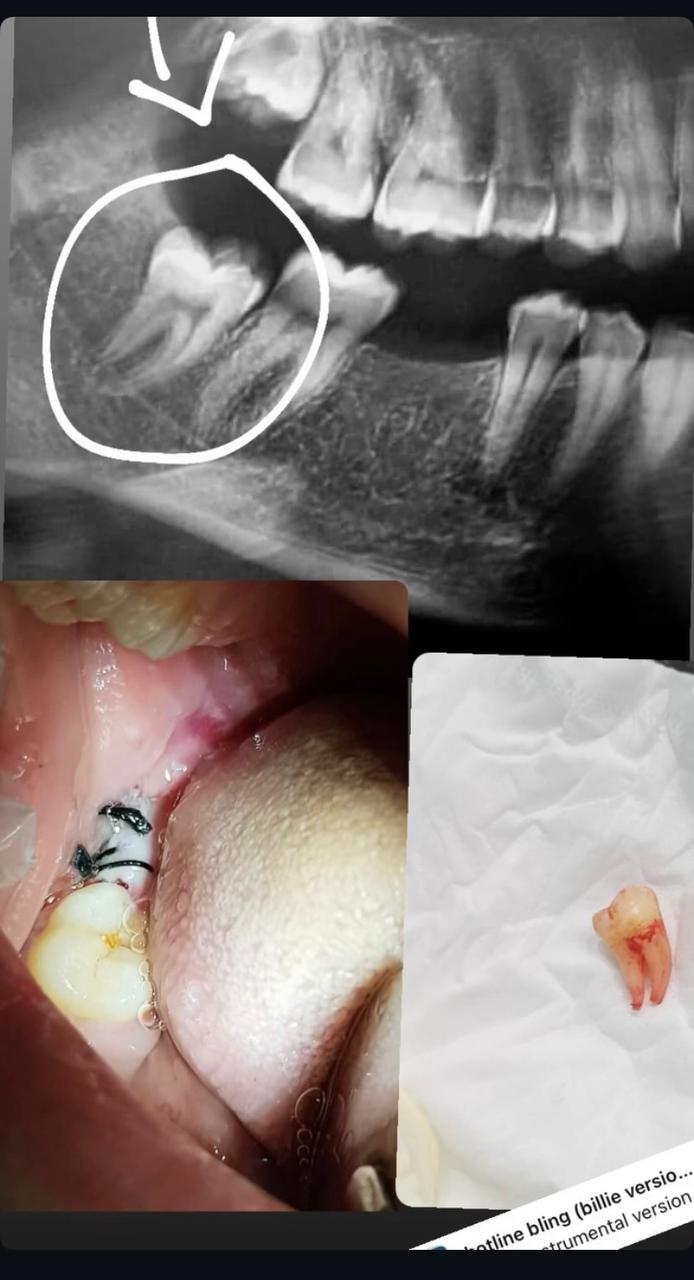

جراحة الأسنان